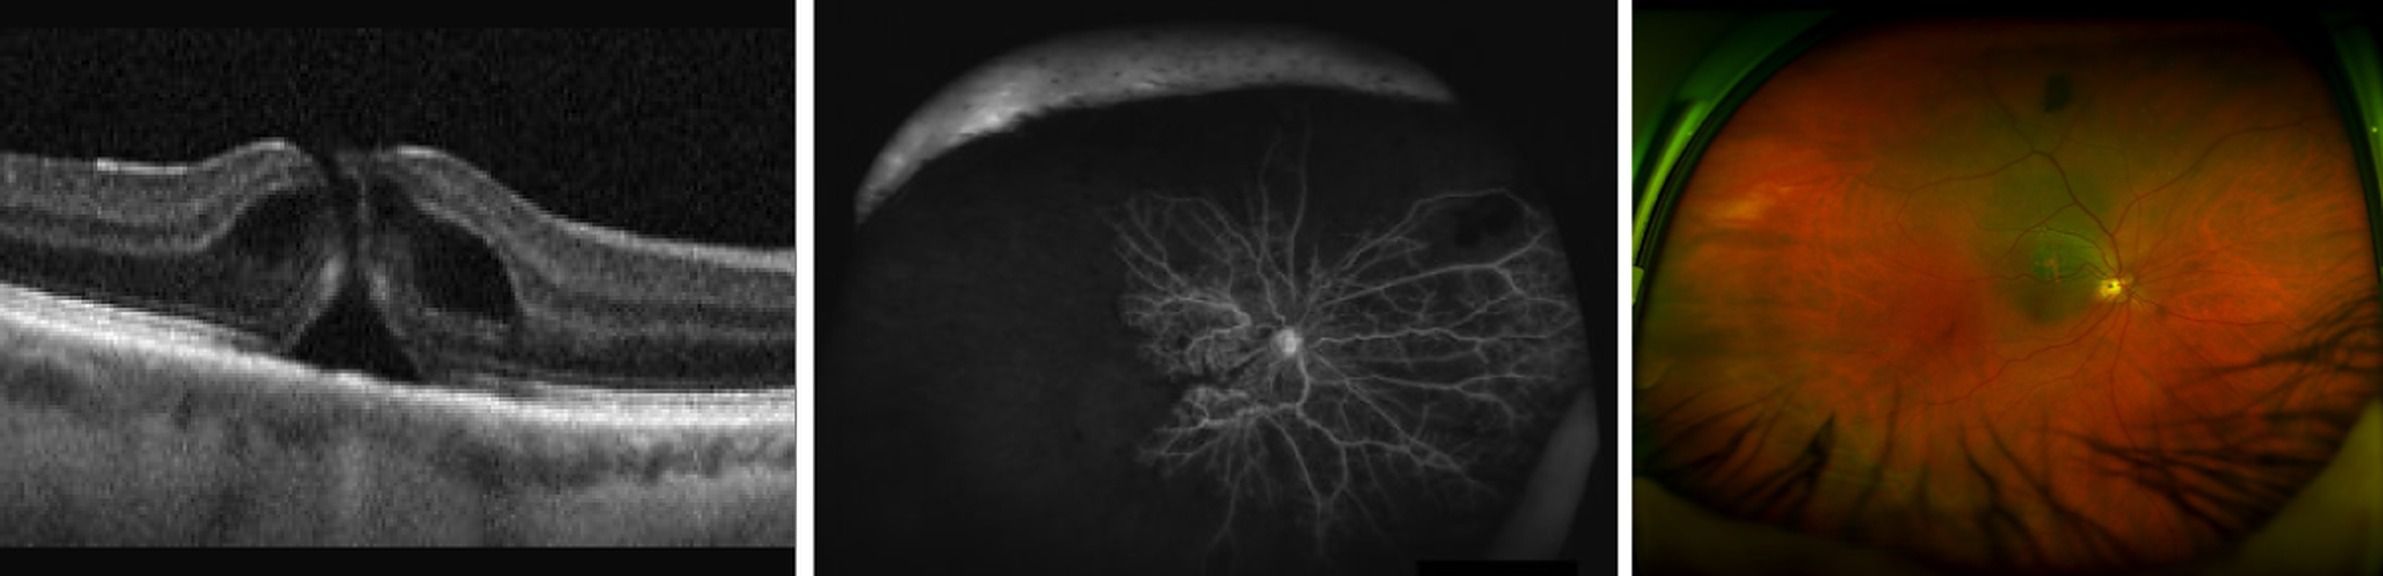

La réalisation d'examen complémentaires du pôle postérieur repose sur l'identification des pathologies rétiniennes telles que les occlusions veineuses rétiniennes ou des pathologies moins fréquentes telles que les tumeurs oculaires.

Dans un premier temps, nous verrons la place de la tomographie par cohérence optique en pratique courante, point de départ pour la réalisation d'autres examens complémentaires plus invasifs (angiographie notamment).

Puis nous détaillerons l'imagerie des occlusions de veines ou de branches rétiniennes, qui sont des pathologies rencontrées en consultation, d'autant plus avec le vieillissement de la population. Il est donc important de connaître les facteurs de risques ainsi que les examens nécessaires au bilan étiologique pour ne pas multiplier les actes inutiles.

Il est indispensable de savoir identifier leurs signes cliniques en imagerie multimodale et surtout savoir prescrire et réaliser les bons examens complémentaires à leurs diagnostics et leurs prises en charge.

Enfin nous aborderons l'apport de l'imagerie multimodale en cancérologie oculaire en présentant les conduites à tenir devant des lésions intraoculaires postérieures d'allure tumorale en utilisant l'imagerie multimodale (échographie oculaire, tomographie à cohérence optique OCT, angiographies à la fluorescéine et en ICG, OCT-Angiographie). Le but est donc d'évaluer si une lésion choroïdienne est a priori d’allure maligne ou bénigne. Ainsi, nous déterminons un arbre décisionnel pour mieux déterminer quelle est la place de chacun des examens et savoir quand les réaliser.